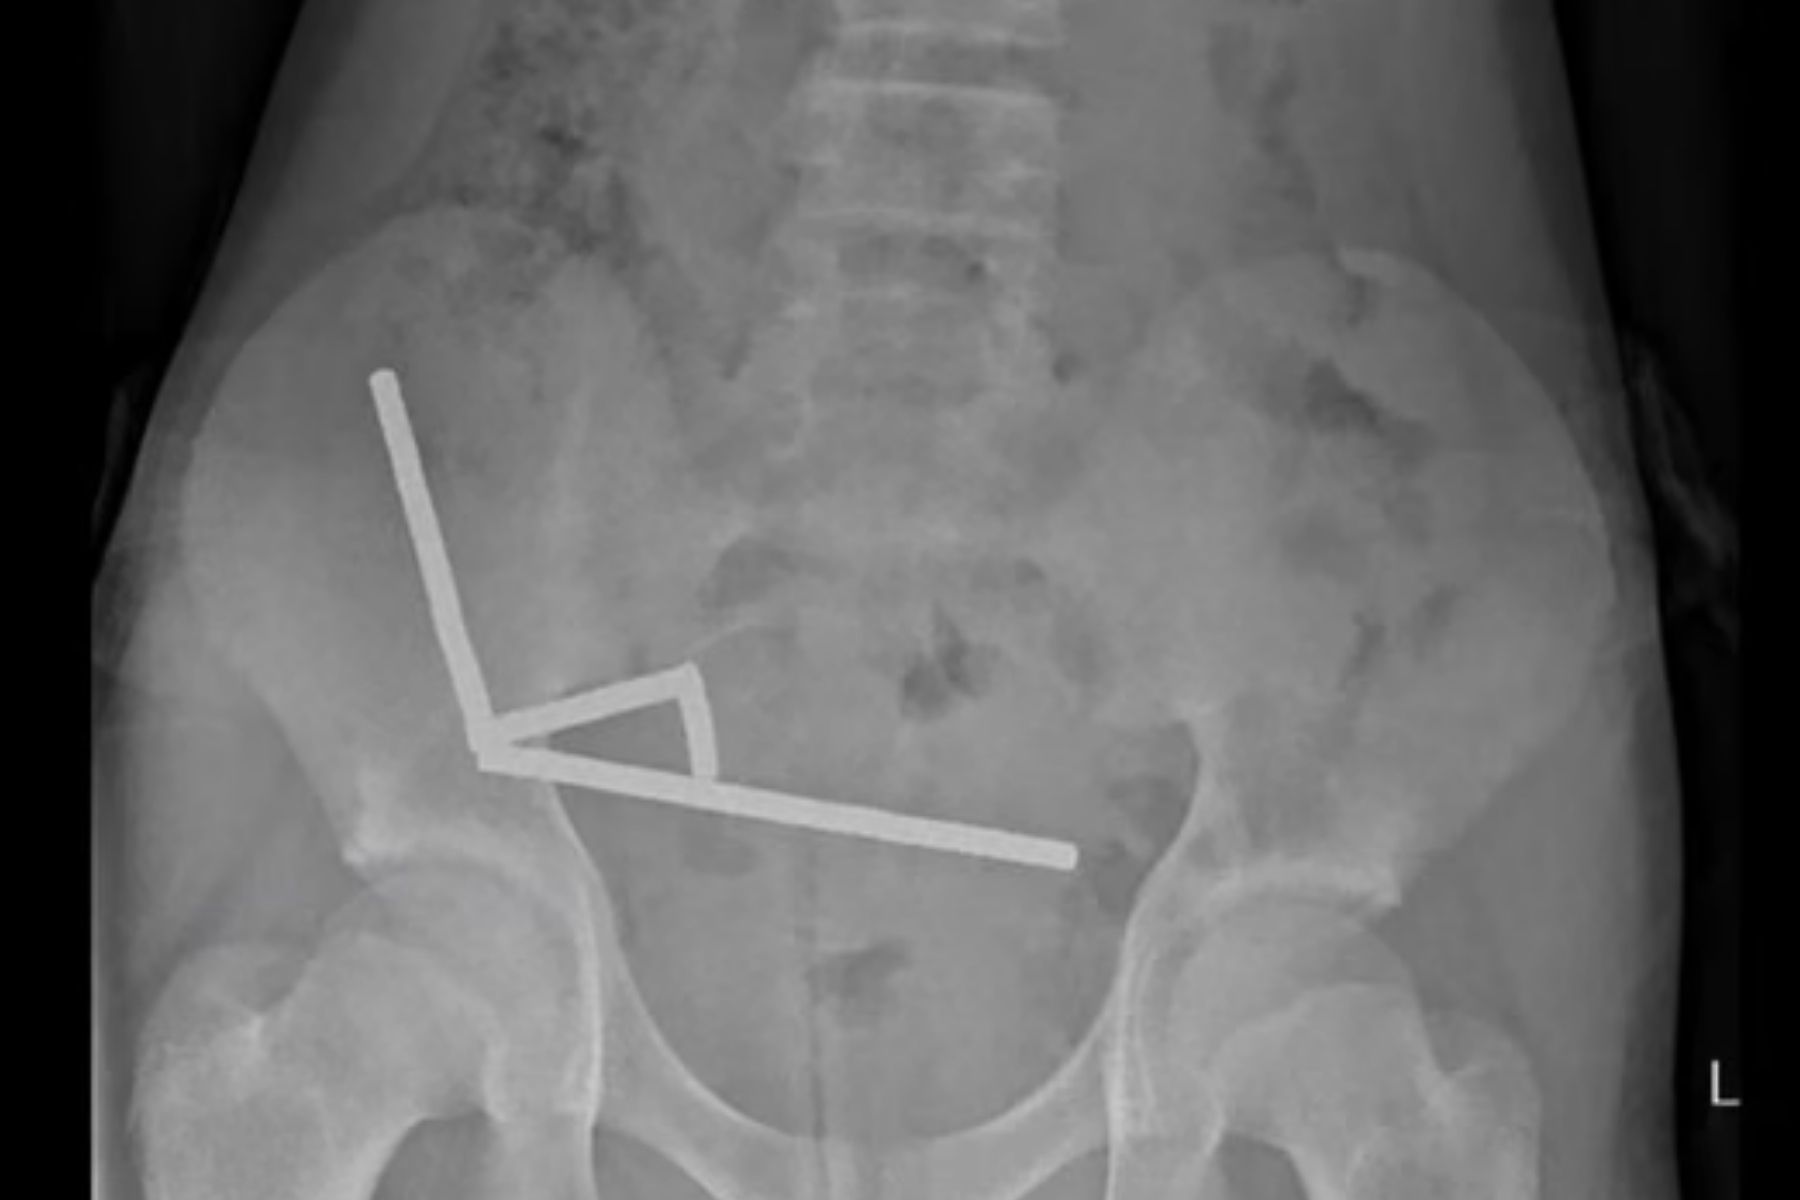

Pemeriksaan rontgen menunjukkan bahwa magnet-magnet itu menempel satu sama lain dan membentuk empat garis lurus di dalam usus sang remaja. Hal ini menyebabkan bagian-bagian usus saling menempel akibat gaya magnet, sehingga menyebabkan kerusakan jaringan.

Tekanan magnet di dalam saluran pencernaan menyebabkan nekrosis, atau kematian jaringan. Nekrosis terjadi pada empat bagian usus halus dan sekum (bagian awal usus besar). Tim bedah pun melakukan operasi untuk mengangkat jaringan mati dan mengeluarkan seluruh magnet dari tubuh pasien.